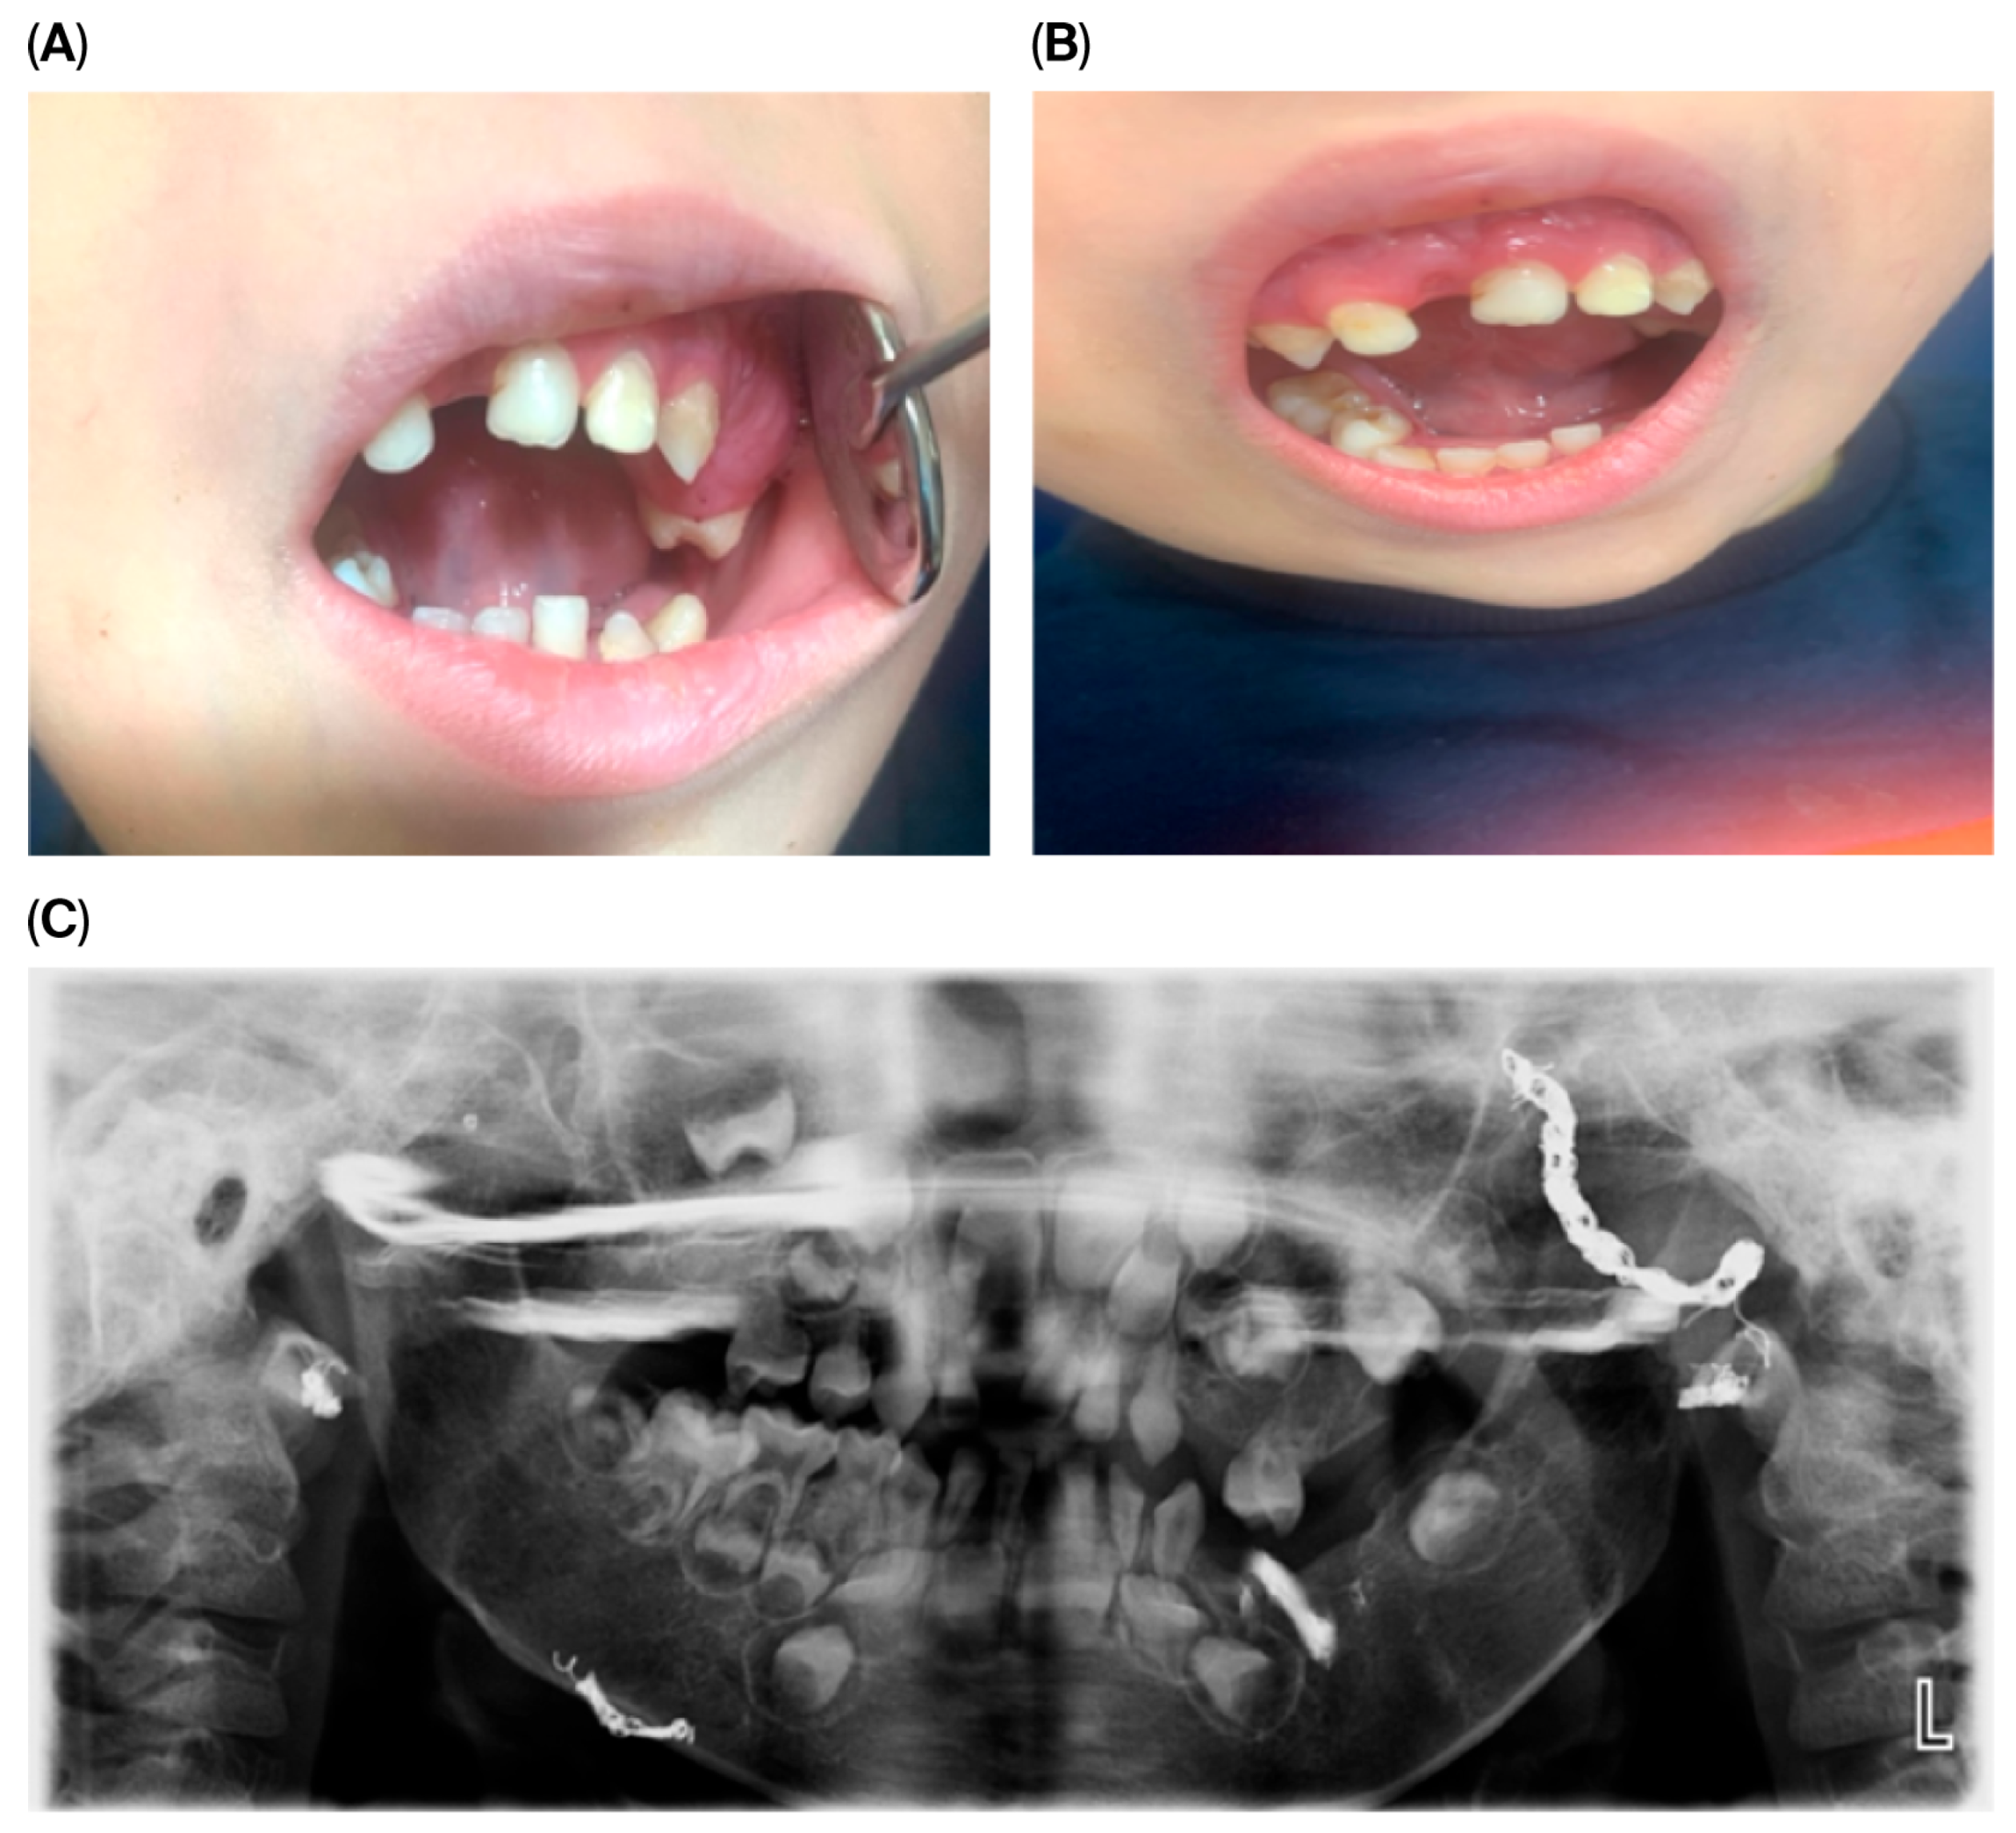

At the most recent dental follow-up, D. has transitioned from full primary dentition to mixed dentition. His permanent maxillary central incisors (teeth 11 and 21) and first molars have erupted, displaying hypoplastic and hypomineralized defects. While these defects are not definitively diagnosed as Turner’s hypoplasia, they are likely attributable to trauma, infection, or previous surgical interventions involving the dental follicles. These teeth were successfully restored with esthetic composite restorations, resulting in significant improvements in both function and appearance. Representative clinical and radiographic findings at ages 6 and 7 are shown in Figure 3.

Figure 3. Intraoral findings at 6 and 7 years of age. (A) Dysplasia of upper central incisors, ectopic teeth, and gingival overgrowth at 6 years of age. (B) Alveolar bone overgrowth in the upper left molar region at 6 years of age. (C) Alveolar bone overgrowth, ectopic teeth, and malocclusion at 7 years of age. (D) Panoramic radiograph at 7 years of age.